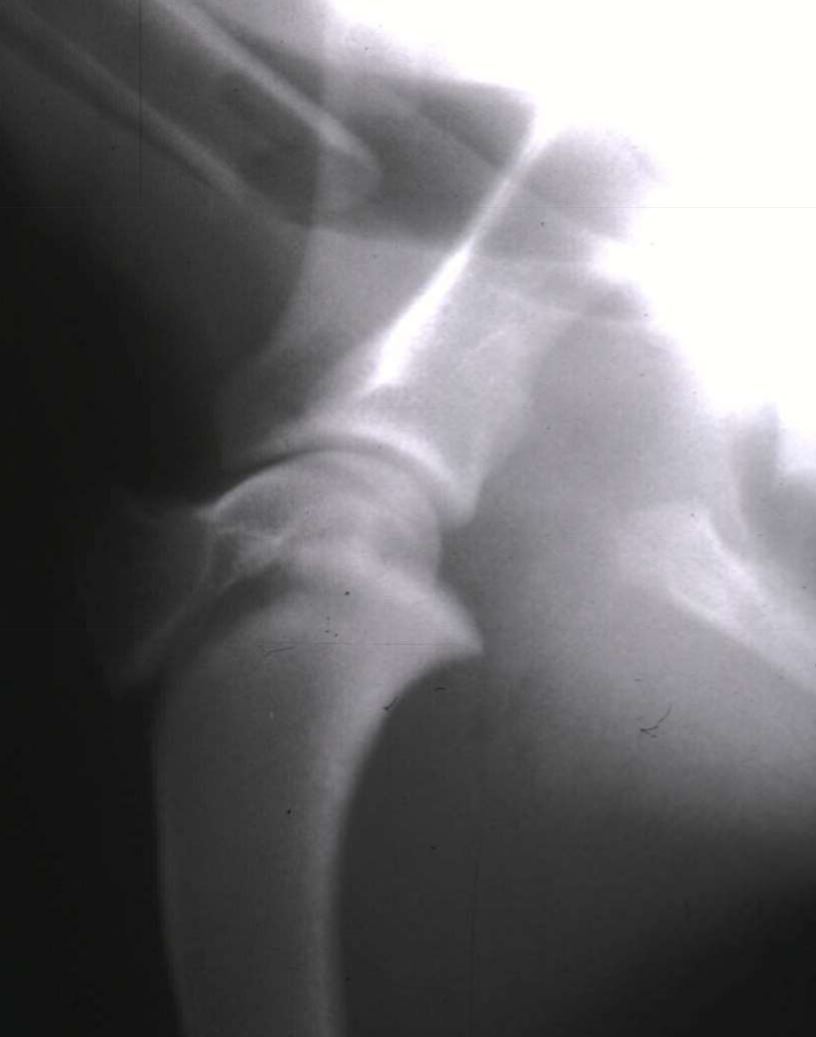

62

11 month old F irish setting, 28kg HBC yesterday Classify and assess fracture, and give repair options

Salter Harris Type 1 (Slip fracture of the femoral head) Fx score= 10 Repair: Diverging pins